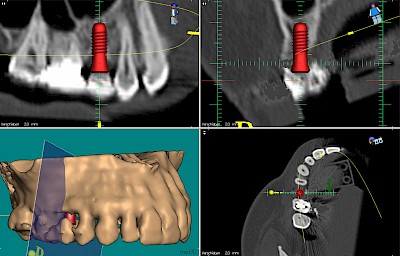

Implantatplanung

Damit Implantate an der richtigen Stelle im Kieferknochen platziert werden könen, gibt es heute vielfältige Möglichkeiten der Planung. In vielen Situationen kann die Erfahrung des Zahnarztes ausreichend sein.

Nicht selten ist jedoch auch eine technisch aufwändigere Vermessung im Vorfeld sinnvoll, z.B.:

- Wenn sich der Kieferknochen abgebaut hat

- Wenn der Nervverlauf im Unterkiefer beachtet werden muss

- Wenn die Ausdehung der Kieferhöhle im Oberkiefer beachtet werden muss

- Wenn wenige Restzähne keine gute Orientierung erlauben

In diesen Fällen kann die Planung mittels verschieden aufwendiger Röntgen-Techniken (Übersichtsaufnahme, DVT) ggf. unter Zuhilfenahme speziell angefertigter Planungsschablonen sinnvoll sein.

Beispiele15 Bilder